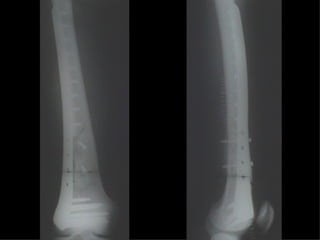

Dal Gennaio 2000 al Febbraio 2006 abbiamo trattato 167 fratture chiuse  con placca percutanea  in 164 pazienti :  27 lesioni diafisarie di gamba, 12 piloni tibiali ,  11 fratture prossimali di tibia, 36 fratture sovracondiloidee di femore, 17 fratture diafisarie di femore, 43 fratture metaepifisarie prossimali di omero, 21 diafisarie d’omero.  156 guarigioni 8 fallimenti

I buoni risultati ottenuti dipendono da 5 punti fondamentali:   una accurata riduzione percutanea della frattura  precise vie di accesso  l’utilizzo della placca che consenta il più lungo braccio di leva possibile il pretensionamento della placca  una sintesi con un ridotto numero di viti

Accurata riduzione percutanea della frattura

Precise vie di accesso

Placche lunghe e pretensionate

Placche lunghe e pretensionate Sintesi con un ridotto numero di viti